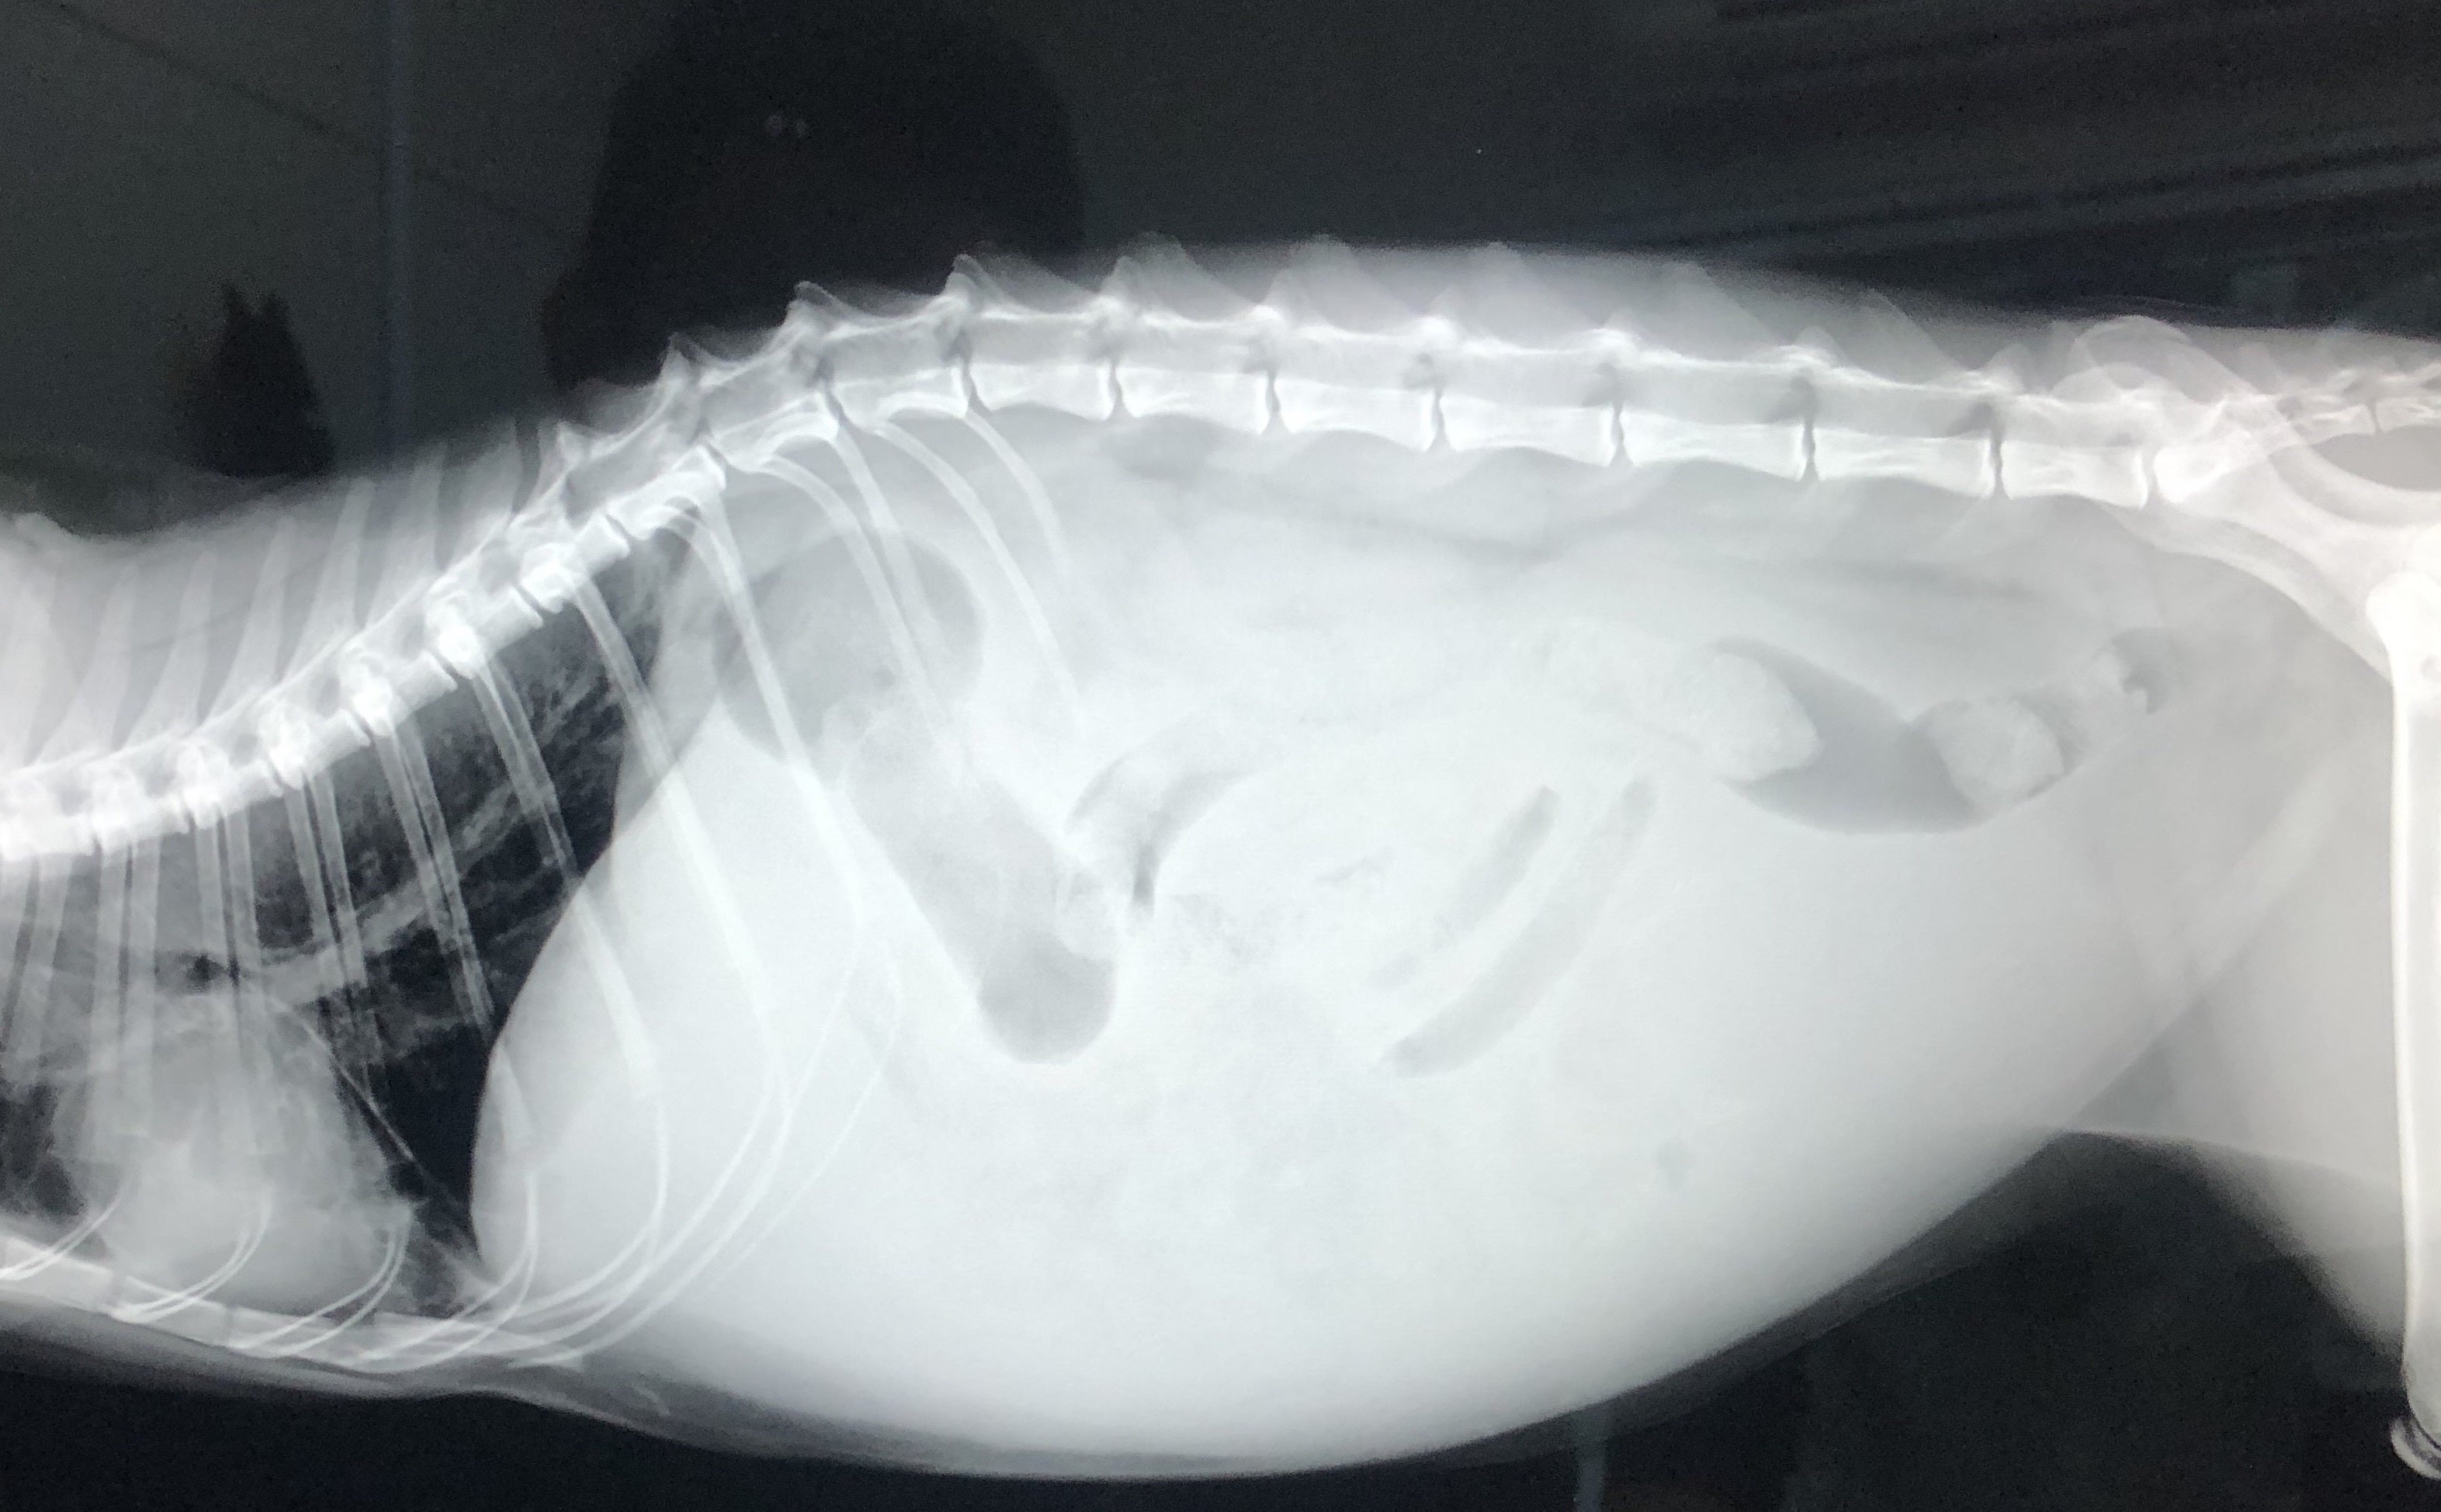

FIPという診断を受けた時に、あらゆる手段を使いこの病気について調べました。動物病院の先生やネットで調べた結果、外猫・野良猫のほとんどが持っているコロナウイルスが突然体内で変異し、FIPウイルスになるということが分かりました。FIPウイルスは一度発症してしまうと元に戻ることはありません。原因はストレスのことが多いと言われており、ずら丸にストレスを与えてしまっていたと日々嘆くばかりです。現在の症状としては腹水・胸水の貯留、食欲減退、便秘、黄疸、脱水症状です。動物病院への通院で脱水症状については収まりを見せていますが、その他は改善の兆しが見えてきません。

腹部レントゲン画像

ずら丸の腹水が溜まっているのを見た際、リンパ癌や心臓の病気など様々な病気を疑いました。しかし考えていたよりも状況は重く、不治の病と言われるFIPでした。世界中にFIPで苦しんでいる猫、オーナー様はいらっしゃいます。新薬での寛解を実証出来れば、今後のオーナー様のFIP治療の選択肢が広がるのではないかと考えています。